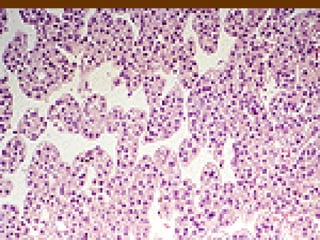

Giải phẫu bệnh của HCC

 Vi thể

- Thể bè

- Thể giả tuyến và tuyến nang

- Thể đảo

- Thể nhú

- Thể đặc

- Thể tế bào sáng

- Thể xơ

- Thể tế bào đa hình thái

- Thể dạng Sacom

Giải phẫu bệnhcủa HCC  Đại thể: - Thể nốt: một nôt hoặc nhiều nốt KT < 5 cm - Thể khối: khối > 5 cm, hay xâm lấn TMC - Thể lan tỏa: lan tỏa khắp gan, KT to nhỏ  Vi thể - Thể bè - Thể giả tuyến và tuyến nang - Thể đảo - Thể nhú - Thể đặc - Thể tế bào sáng - Thể xơ - Thể tế bào đa hình thái - Thể dạng Sacom